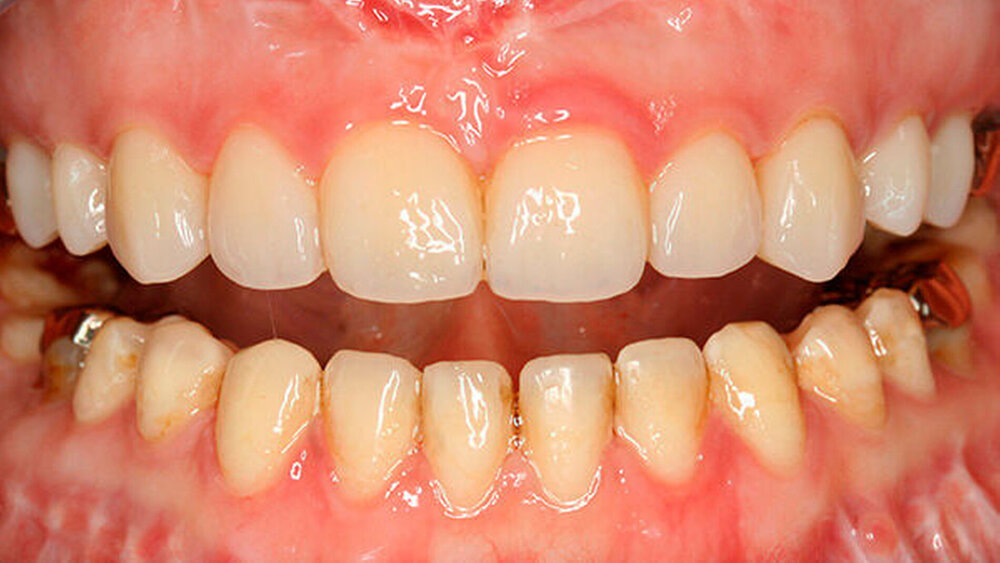

Die Patientin äußerte den Wunsch, die Behandlung in möglichst wenige Sitzungen aufzuteilen. Deshalb wurden im Oberkiefer alle Zähne - mit Ausnahme der mit Gold versorgten Molaren - innerhalb einer längeren Sitzung präpariert (Abbildung 7).

Im Nachhinein stellte sich das getrennte Vorgehen für Ober- und Unterkiefer als durchaus hilfreich für die Patientin dar, die schon nach Einsetzen der Restaurationen im Oberkiefer den Eindruck hatte, nun regelmäßig in eine klar definierte maximale Interkuspidation finden zu können.

Nach Eingliedern der Restaurationen im Unterkiefer trat in dieser Hinsicht nochmalige Besserung ein. Möglicherweise war weiterhin hilfreich, dass die Goldrestaurationen zunächst belassen wurden, da sie im Labor eine Zuordnung der Modelle erleichterten.

Das Konditionieren der Restauration erfolgte mittels Aluminiumsilikat (CoJet™ Verbundsystem und CoJet™ Sand, 3M ESPE) und anschließender Silanisierung der Innenseite (Monobond Plus, Ivoclar Vivadent). Nach Einpassung der Restauration wurde eine initiale Lichthärtung durchgeführt, Überschüsse entfernt und abschließend erneut polymerisert. Zuletzt wurden die Ränder der Restauration geglättet (Brownie und Greenie, Shofu Dental GmbH) und die Okklusion überprüft (Abbildungen 8 bis 11).